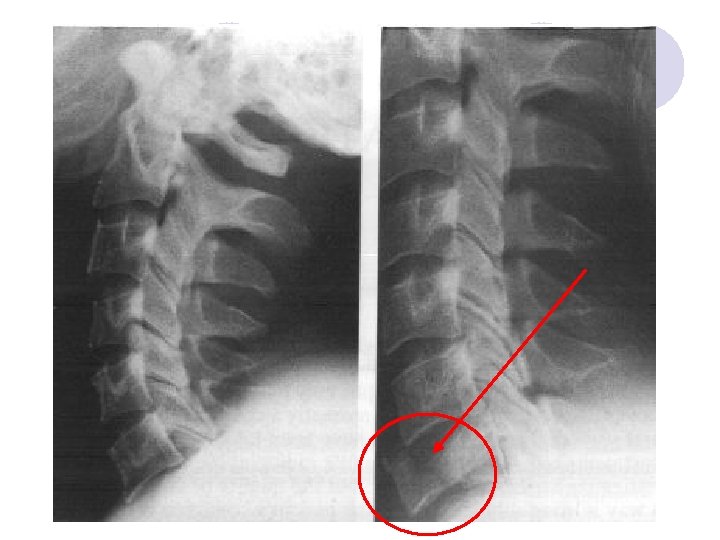

FRACTURA DEL AHORCADO

SOSPECHAR LESION CERVICAL HASTA QUE SE DEMUESTRE LO CONTRARIO l l l Trauma severo Dolor de la zona Conciencia alterada No sospecharla riesgo de lesión sobreagregada Sospechar implica inmovilización protectora adecuada ¡ Collar + cojín cervical lateral ¡ Tabla espinal + fijación

Mecanismo del Trauma Identificar el vector de fuerza principal Ojo con las lesiones multidireccionales!

MANEJO INICIAL DEL TRAUMA ABC l Protección vía aérea => inmovilización l Respiratorio ¡ Parálisis respiratoria en lesión sobre C 5 ¡ O 2, intubación precoz en lesión C 4 o superior ¡ Atelectasia + falla respiratoria en lesión cervical l Protocolo metilprednisolona < 8 hrs accidente l